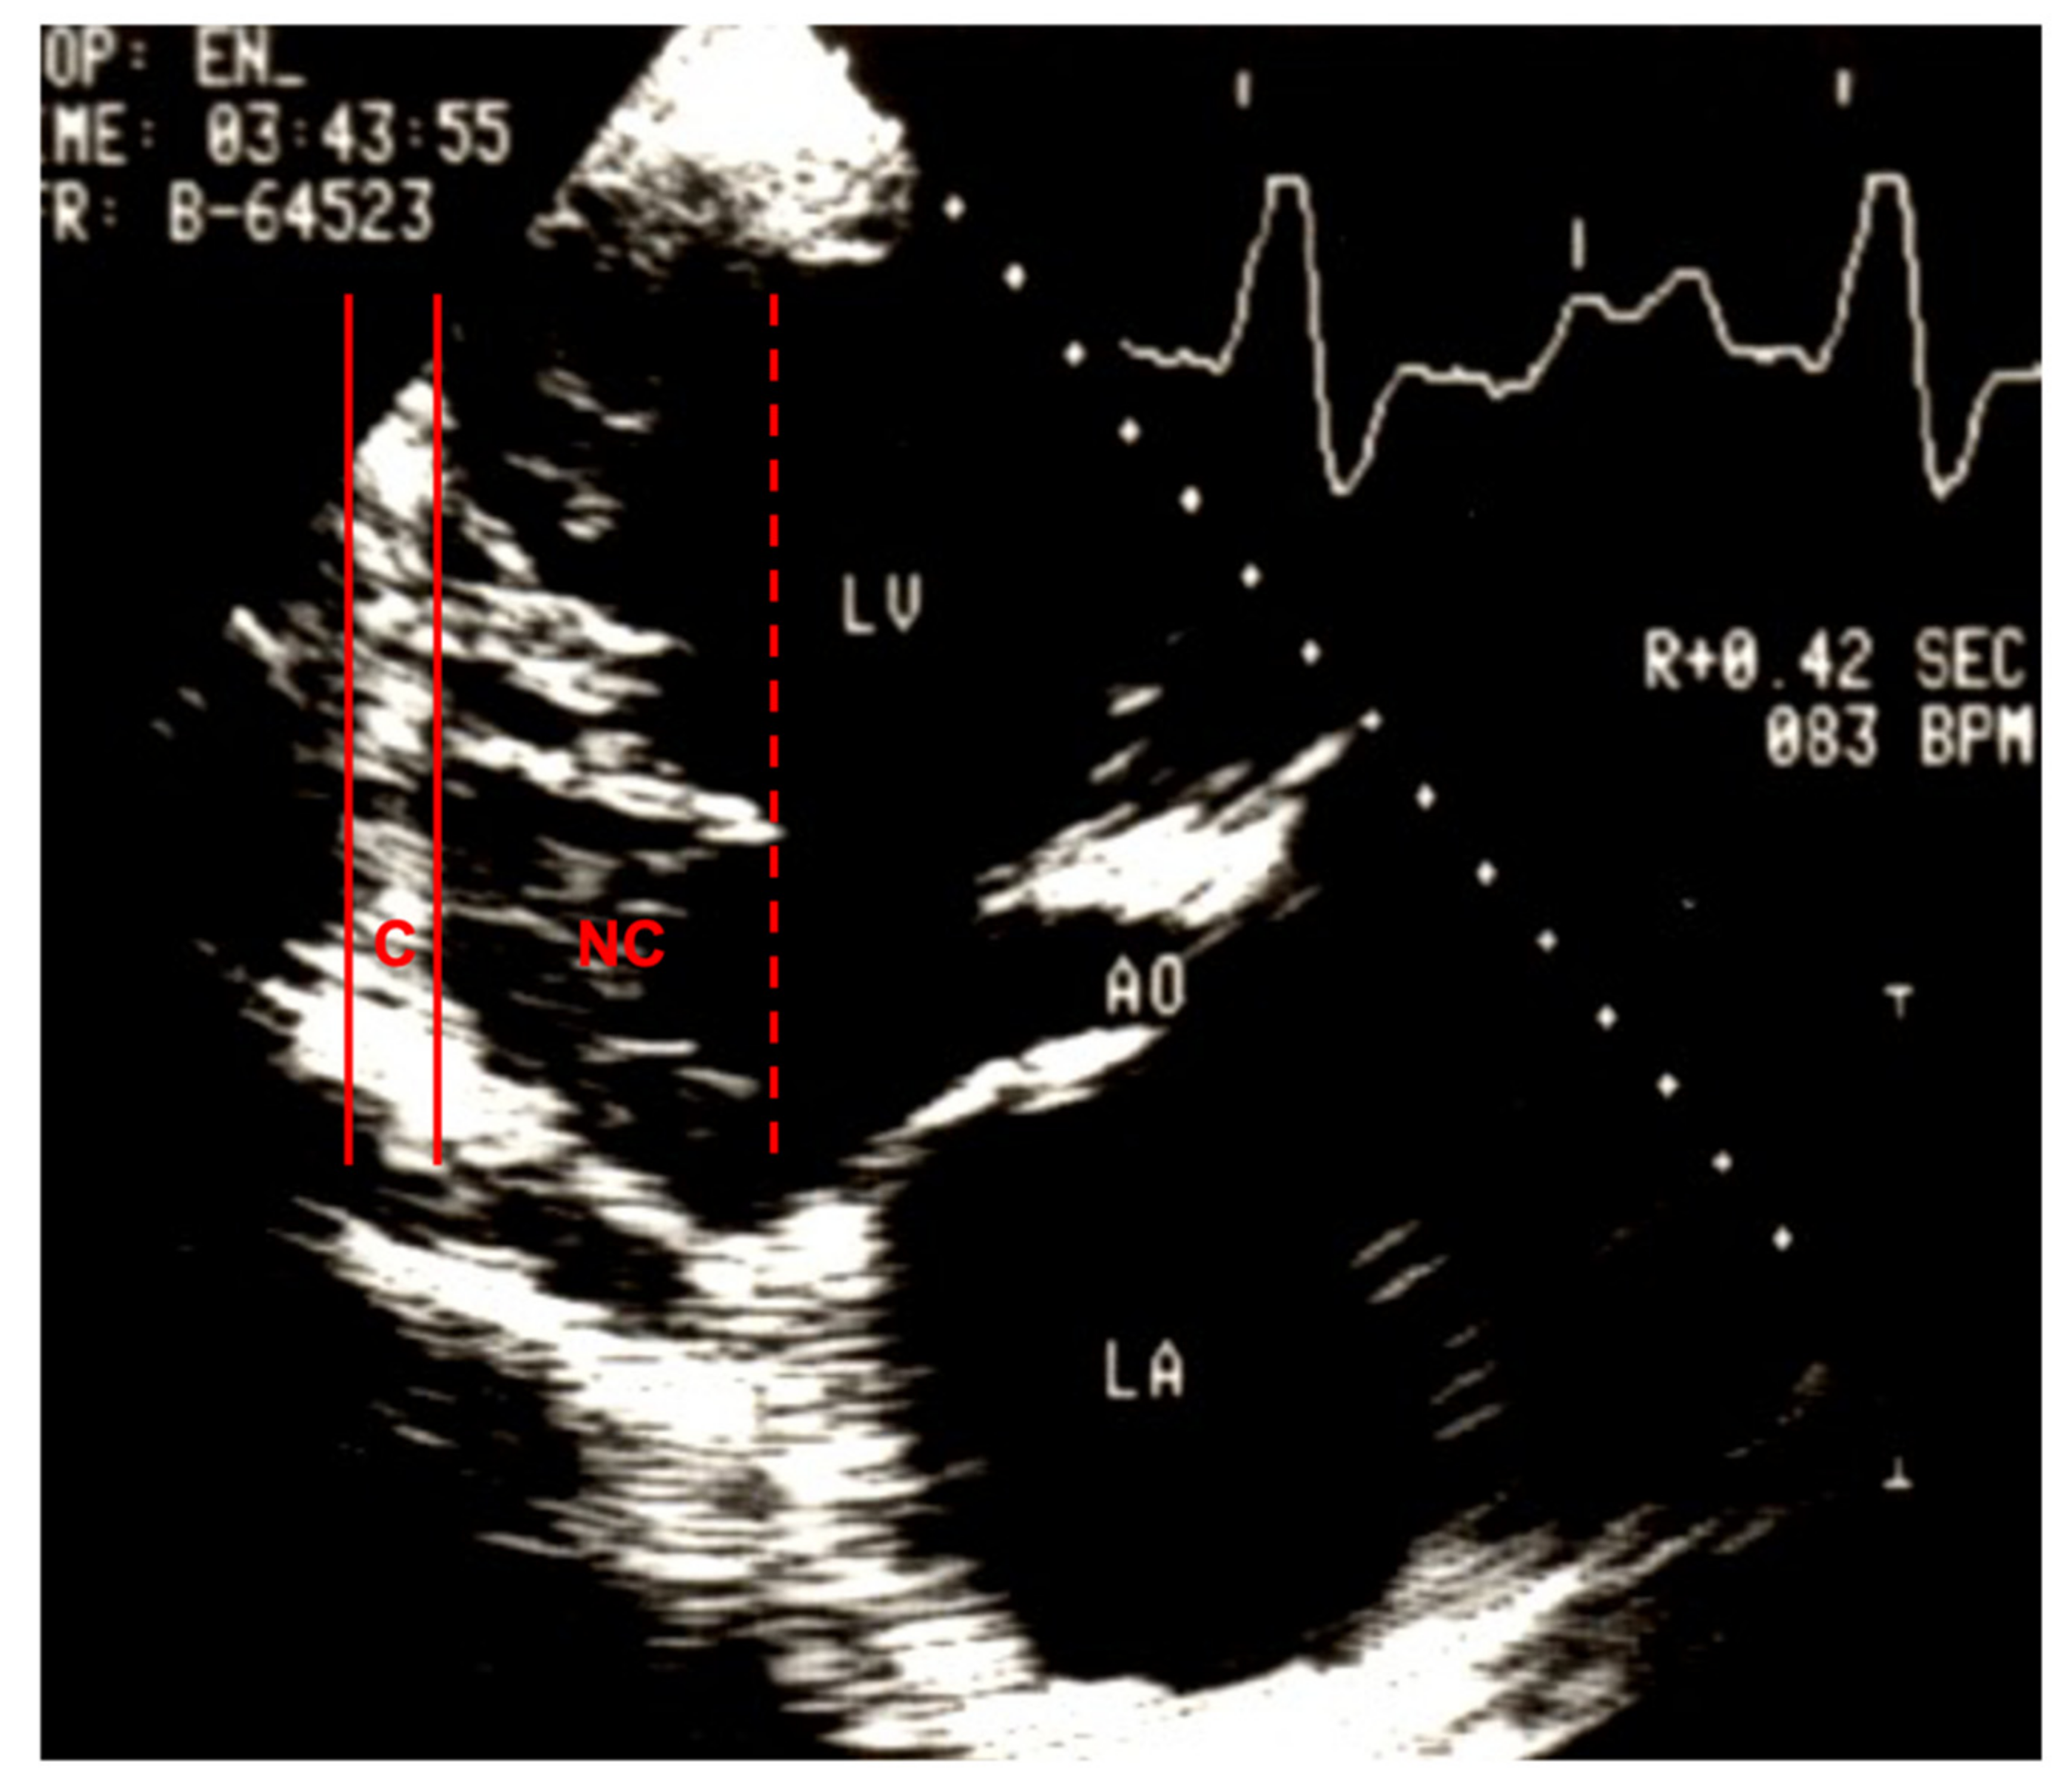

1. At least four prominent trabeculations and deep intertrabecular recesses; |

2. Blood flow between the cavity of the left ventricle and the recesses demonstrable by color Doppler echocardiography or by the use of ultrasonographic contrast medium; |

3. The left ventricular wall segments show a typical bilaminar structure, and the noncompact subendocardial layer is at least twice as thick as the compact subepicardial layer in systole; |

4. No other cardiac abnormalities present. |

| Jenni 2001; [8,78] | Zurich | Excessive prominent trabeculations | Deep intertrabecular recesses | Compacted thin epicardial and much thicker noncompacted endocardial | NC/C > 2 | Abnormalities absent | Perfused recesses in color Doppler | End systole | Short axis view |

| Engberding 2007; [62] | Germany | At least 4 prominent trabeculations | Deep intertrabecular recesses | Bilaminar structure | NC/C ≥ 2 | No other cardiac abnormalities | Blood flow in recesses in color Doppler or with echo contrast | Systole | |